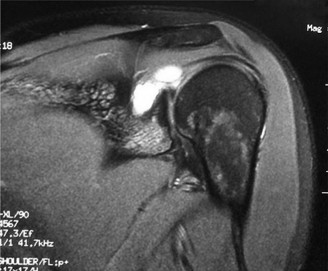

Treat a patient with scapular winging? CASE 23 A 47-year-old, right-hand-dominant male presents to your clinic complaining of right shoulder weakness for the past 2 months. He denies any history of trauma but notes sudden onset of pain 2 months ago that lasted approximately 2 weeks and then subsided without any intervention and was followed by shoulder weakness. He works as a lawyer and has been going through a divorce for the past year. Physical examination reveals no tenderness to palpation about the shoulder. He has decreased sensation over the lateral aspect of the shoulder, decreased muscle bulk over the left shoulder compared with the contralateral side, and weakness with left shoulder abduction. He is distally neurovascularly intact. The patient had already been referred for an x-ray and MRI by his primary care doctor that are shown in Figures 2–62 and 2–63.

Figure 2–62

Figure 2–63

The correct answer is (C). The patient’s decreased sensation over the deltoid, deltoid muscle atrophy on examination, and MRI with atrophy of the teres minor points to axillary nerve dysfunction. Suprascapular nerve injury (Choice A) would result in atrophy of the infraspinatus and or infraspinatus muscles, leading to weakness with external rotation and/or forward flexion. Dorsal scapular nerve injury (Choice B) would result in weakness of the rhomboid muscles and levator scapulae. While injury to the posterior cord of the brachial plexus (Choice D) would result in symptoms of axillary nerve palsy, they would also involve dysfunction of the radial nerve, which also comes off the posterior cord.

The correct answer is (B). Parsonage Turner syndrome (brachial neuritis) is characterized by acute brachial neuropathy which can affect different nerves of the brachial plexus. In this patient, it is the most likely explanation for his atraumatic deltoid paralysis with axillary nerve palsy in a time of severe stress. The cause of Parsonage Turner Syndrome is unknown, but it has been associated with severe stress and viral infection. Quadrilateral space syndrome (Choice A) involves entrapment of the axillary nerve as it passes through the quadrilateral space, would present as chronic dull pain, and is usually not associated with decreased sensation. While Choices C and D can both be a cause of axillary nerve injury, the patient has no history of trauma and there are no masses on his MRI.